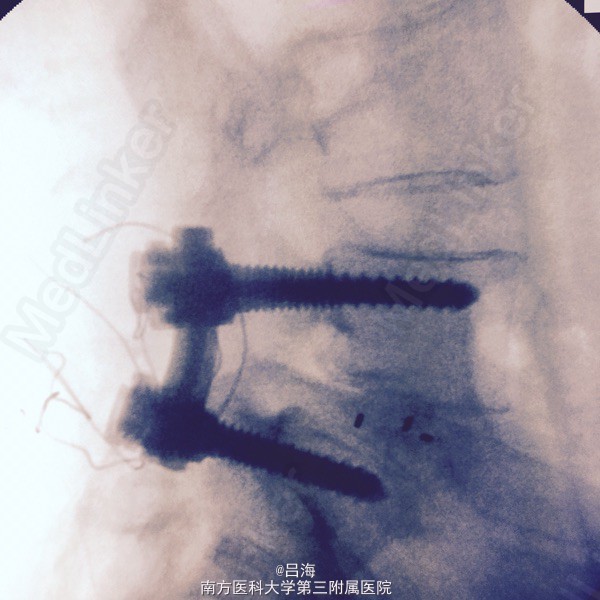

腰5椎体II度滑脱并峡部裂;椎管狭窄症。 后路腰5全椎板切除减压,滑脱复位,椎间cage植骨融合,经椎弓根内固定术

术后症状缓解 术中要求减压彻底,全椎板切除,显露、减压双侧腰5骶1神经根,撬拨辅助复位,但不强求复位。